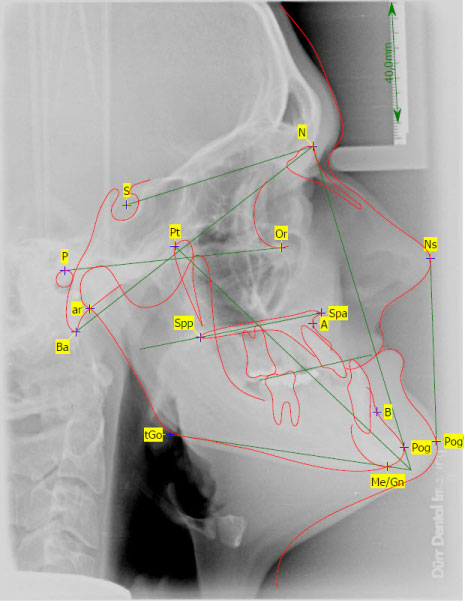

In November 2007, a male patient with ICD10 (K00.0; K07.1) asked for treatment. The diagnosis included craniomandibular malfunction, dysgnathia class III, maxillary retrognathia with horizontal and transverse narrowing of the maxilla, mandibular prognathia with lingual tipping of the mandibular front teeth (Figure 1). Additionally, we diagnosed multiple missing of permanent teeth and hypodontia of deciduous teeth with cones (Figure 2, Figure 3 and Figure 4). Systemically, the patient suffered from platelet deficiency and thrombocytopenia.

Figure 4: Cephalometric X-ray (lateral view) with facial analysis before treatment. View Figure 4